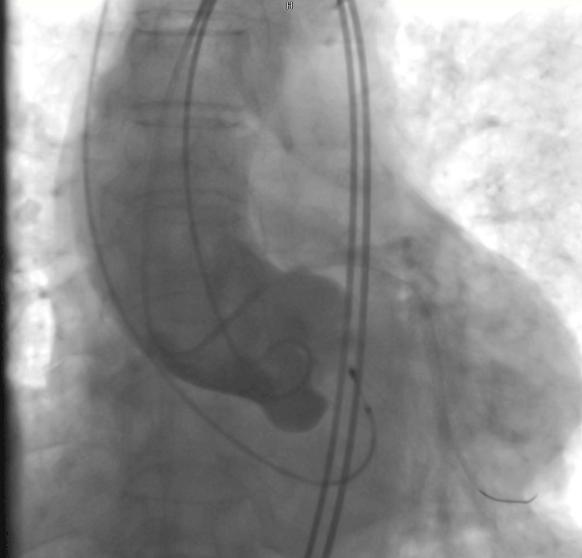

术中,在DSA(数字减影血管造影)严密实时监测下,何晋主任医师从杨爷爷大腿根部股动脉穿刺,通过大血管将主动脉支架瓣膜及装置输送到病变的主动脉瓣位置,缓缓释放支架瓣膜,经过精密调控,支架瓣膜精确植入,原先狭窄的瓣膜口子一下就开通了,术中监测主动脉瓣和心室压差为零。